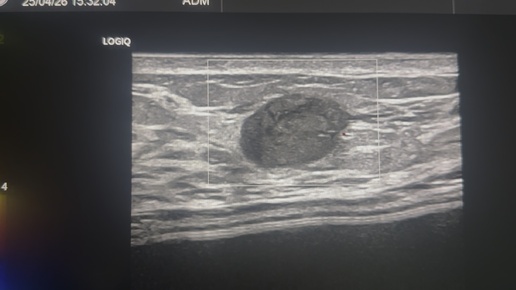

Фиброаденома молочной железы с кровотоком